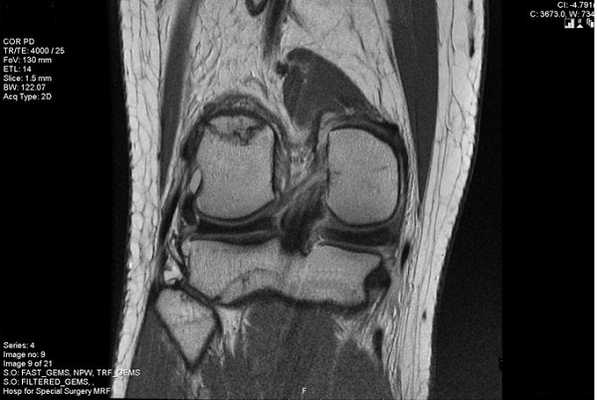

Повреждение медиального хряща на снимке МРТ

МРТ мениска коленного сустава визуализирует степень поражения хрящевой прослойки и показывает сопутствующие изменения в строении сочленения. Суть метода заключается в воздействии магнитного поля на атомы водорода в молекулах воды. Заряженные частицы резонируют, обеспечивая отклик сканируемых структур. Интенсивность ответной реакции зависит от насыщенности тканей жидкостью. МРТ рыхлых анатомических образований обладает большей информативностью по сравнению с костными тканями.

Разрыв заднего рога медиального мениска на снимке МРТ

Лечение зависит от степени поражения. При I и II специалисты рекомендуют консервативные методы и покой, III стадия требует хирургического вмешательства.

Признаком повреждения мениска служит наличие линейного гиперинтенсивного очага на Т2-взвешенных изображениях. Участок сообщается с суставной поверхностью хряща, линию разрыва прослеживают на двух и более сканируемых срезах. При этом наблюдают деформацию и фрагментацию пластины.

Томограмма коленного сустава при радиальном разрыве мениска (указан стрелкой)

В зависимости от степени повреждения на снимках МРТ в режиме Т2 видны:

- очаг повышения интенсивности сигнала шаровидной формы, не связанный с поверхностью мениска (I стадия);

- светлый участок линейной формы, не затрагивающий хрящевой край (II стадия);

- повышение интенсивности сигнала распространяется на одну (III a) или обе (III b стадия) суставные поверхности пластины.

Разрыв заднего рога медиального хряща на снимках, выполненных в разных режимах, стрелка указывает на нарушение целостности пластины